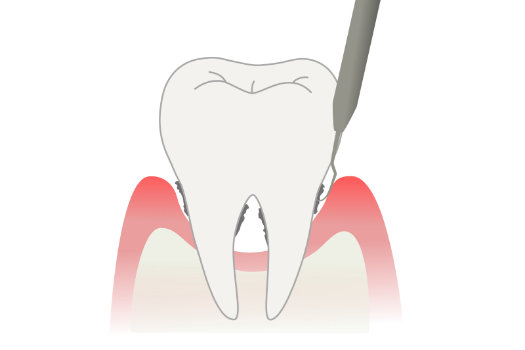

C4:歯根にまで進行

虫歯が歯根に達した状態。神経が死んでいるため痛みは感じませんが、化膿すると再度激しく痛みます。

ほとんどの場合において、抜歯が必要です。歯を失った部分には入れ歯やインプラントで補完します。